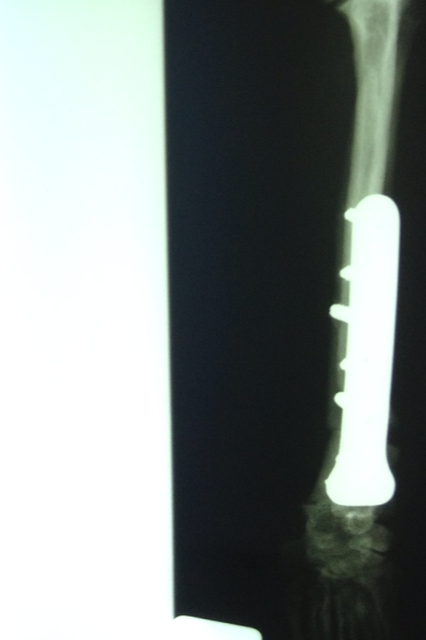

Felipas erste Operation

06Heute hatte Felipa ihren ersten OP-Termin.

Wir waren alle sehr aufgeregt. Und selbst der erfahrene Arzt meinte, es sei eine ungewöhnliche Aktion, denn normalerweise weist nur ein Pfötchen so starke Anomalien auf. Er hatte es noch nicht, dass beide operiert werden müssen.

Felipa war relativ unbeeindruckt von der ganzen Geschichte und tanzte schon kurz nach dem Eingriff wieder auf dem Tisch herum.

In sechs Wochen erfolgt dann die zweite OP.

Wir danken herzlich für die Geldspenden, die dies alles erst ermöglicht haben - aber bitten auch dringend um weitere Überweisungen, denn wir mussten heute auch Griffin operieren lassen, der sich mit Kniescheibenproblemen herumplagte. Und weil Lucy auch Probleme zu haben scheint, haben wir sie heute mitgenommen zum Röntgen. Es stellte sich leider heraus, dass sie einen Kreuzbandriss hat, der ebenfalls operiert werden muss.